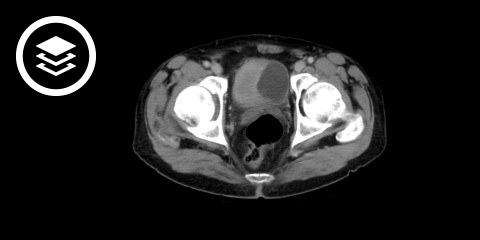

Bei einem muskelinvasiven Harnblasenkarzinom müssen weitere Herde im Harntrakt augeschlossen werden. Daher wird eine CT des Abdomens (mit CT-Urographie), des Beckens und des Thorax mit Kontrastmittel durchgeführt. Die CT des Beckens kann durch eine MRT-Untersuchung ersetzt werden. Bei klinischen Hinweisen kann eine kraniale CT oder eine Knochenszintigraphie indiziert sein.

CT-Fallbeispiel

- Bildquelle DICOM-Viewer: Kirk et al. (2016). The Cancer Genome Atlas Urothelial Bladder Carcinoma Collection (TCGA-BLCA) (Version 8). The Cancer Imaging Archive.